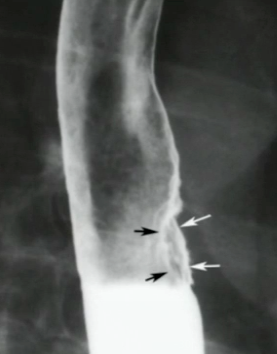

What is your diagnosis?

Schatzki ring. Normally you give a 13mm ring and if that cannot pass they need to be dilated.

Reflux esophagitis. Note the multiple tiny ulcerations.

What are these all signs of?

Fixed transverse folds, feline esophagus and tertiary waves are all associated with reflux esophagitis or eosinophilic esophagitis.

Why do you keep an eye on this condition?

This is Barrett esophagus. It is precancerous.